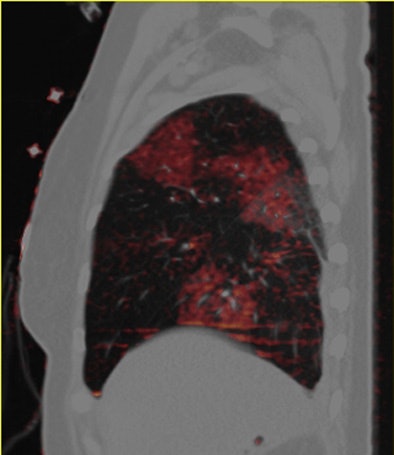

Dual-energy CT enables the selective display of iodine distribution within the pulmonary parenchyma following contrast-enhanced pulmonary CT angiography, which in turn permits the calculation of perfusion defect (PD) size in patients with suspected PE.

Depending on the shape and pattern of the defects at dual-energy CT, perfusion defects due to PE can generally be distinguished from, for example, patchy defects signaling other pathologies of the lung parenchyma, Bauer said.

The researchers measured perfusion defect size in the lung parenchyma caused by PE on dual-energy iodine distribution maps, and expressed it in two ways: as absolute quantification (VolPD in mL) and relative to the total lung volume (RelPD in %).

| Patient with bilateral segmental and subsegmental PE and large perfusion defects on dual-energy iodine distribution maps. All images courtesy of Dr. Ralf Bauer. |